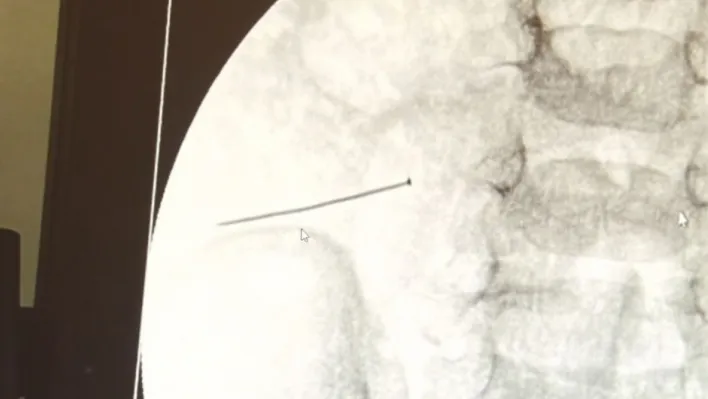

İstanbul’da 2 yaşındaki çocuk iddiaya göre toplu iğne yuttu sonrasında adeta karın ağrısıyla yerinde duramaz hale geldi. Babaanne, küçük çocuğun şikayetleri üzerine Şehit Prof. Dr. İlhan Varank Sancaktepe Eğitim ve Araştırma Hastanesi’ne götürdü. Burada yapılan tetkiklerde 2 yaşındaki çocuğun ince bağırsağında yaklaşık 3 santimlik toplu iğne olduğu ve bağırsağı deldiği belirlendi. Görüntülemeler sonrası 30 Ekim akşamı Çocuk Cerrahisi Kliniği Eğitim ve İdari Sorumlusu Doç. Dr. Sefa Sağ ve ekibi hemen ameliyata girdi. Başarılı operasyonla iğne olduğu noktadan alınırken aile de rahat bir nefes aldı. Doç. Dr. Sağ ise taburcu edilen hastasının durumuna ilişkin bilgi verirken yabancı cisim yutmalarına karşı ailelere önemli uyarılarda bulundu.

Çocuklarda yabancı cisim yutulmasına yönelik konuşan ve hastasına ilişkin bilgi veren Doç. Dr. Sefa Sağ, "Soluk borusuna kaçması durumunda çocuğun Allah göstermesin ölümüyle veya ömür boyunca yatağa bağımlı kalmasıyla neticelenebilecek sonuçlar doğurabiliyor. Yutulması durumunda da gastrointestinal sistemin herhangi bir yerine takılmadığı müddetçe ekseriyâ yabancı cisimlerin dışarıya çıkmasını bekliyoruz. Yabancı cisim yutulmasını 2 grupta inceleyebiliriz. Sıvı ve katı cisimler olarak sıvı; evde kullanılan kimyasal temizlik malzemelerinin yutulması çok ciddi problemler oluşturabilmekte. Ağızda, yemek borusunda ve midede yanıklar meydana getirebilmekte. Uzun dönemde çocukların hayat kalitesini oldukça etkileyen sonuçlar doğurabilmekte. Katı cisimlerden de ekseriyâ kendiliğinden çıkmasını bekleriz ancak böyle delici, kesici aletlerin yutulmasında ise herhangi bir bağırsağın veya gastrointestinal sistemin bir parçasında delinmeler meydana getirebiliyor. Bu çocuğumuzda da aynen böyle bir hadise meydana gelmişti. Sanırım 1 gün önce ailenin yuttuğunu tahmin ettiği bir yabancı cisim; toplu iğne. Ertesi gün bağırsakta delinmeyle sonuçlanmış ve çocukta da ciddi semptomlar meydana getirmişti. Bu şekilde hasta bize başvurdu. Tetkikler sonucunda yabancı cismi tespit ettik, semptomları ve bulgularına göre de çocuğu ameliyata aldık. Yaklaşık 3 santim boyunda bir toplu iğnenin ince bağırsağı deldiğini, ince bağırsaktaki içeriğin de karın içerisine dolduğunu gördük. Ameliyatı başarılı bir şekilde tamamladık, yaklaşık 1 saat süren bir ameliyattı" dedi.

Öte yandan, yaklaşık 3 santimlik toplu iğne filme yansıyan görüntüsüyle gözler önüne serildi.